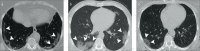

Results: A total of 250 patients were finally diagnosed with COVID-19. Clinical and laboratory findings included myalgia or fatigue (76%), fever (64.8%), dry cough (60.8%), elevated levels of C-reactive protein (86.4%), procalcitonin (62%), and D-dimer (58.2%), increased neutrophil-lymphocyte ratio (NLR) (54.8%), and lymphopenia (34%). Sensitivity, specificity, positive predictive value (PPV) and negative predictive value (NPV) of the initial CT scan were 90.4% (95% IC, 86%-93%), 64.2% (95% IC, 50%-76%), 91.8% (95% IC, 88%-94%), and 60% (95% IC, 49%-69%), respectively. The percentage of patients diagnosed on the initial rRT-PCR test was 51.6% (n=129). Most frequent CT characteristics of COVID-19 in the subgroup of rRT-PCR-positive patients were multiple lesion (97.4%, n=220), followed by bilateral involvement (88.5%, n=200), peripheral distribution (74.3%, n=168), ground-glass opacity (GGO) (69.2%, n=157), subpleural curvilinear opacity (41.6%, n=104), and mixed GGOs (27.6%, n=67).